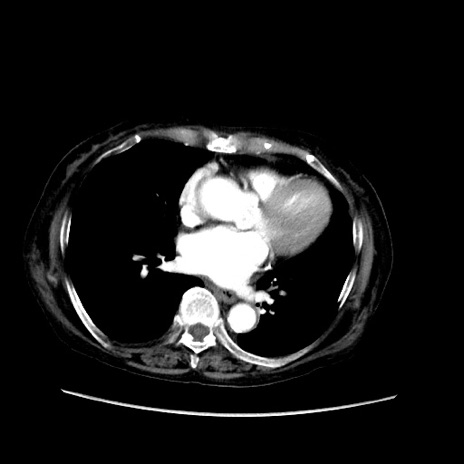

症例31(横断像)

【症例】80歳代 女性

【主訴】腹部膨満感

【現病歴】他院にて肝硬変にてフォロー中。1週間前から便秘、腹部膨満感、臍部腫瘤あり受診となる。

【既往歴】肝硬変

【身体所見】腹部膨隆あり、皮膚変化なし、疼痛なし。

【データ】WBC 4600、CRP 0.25